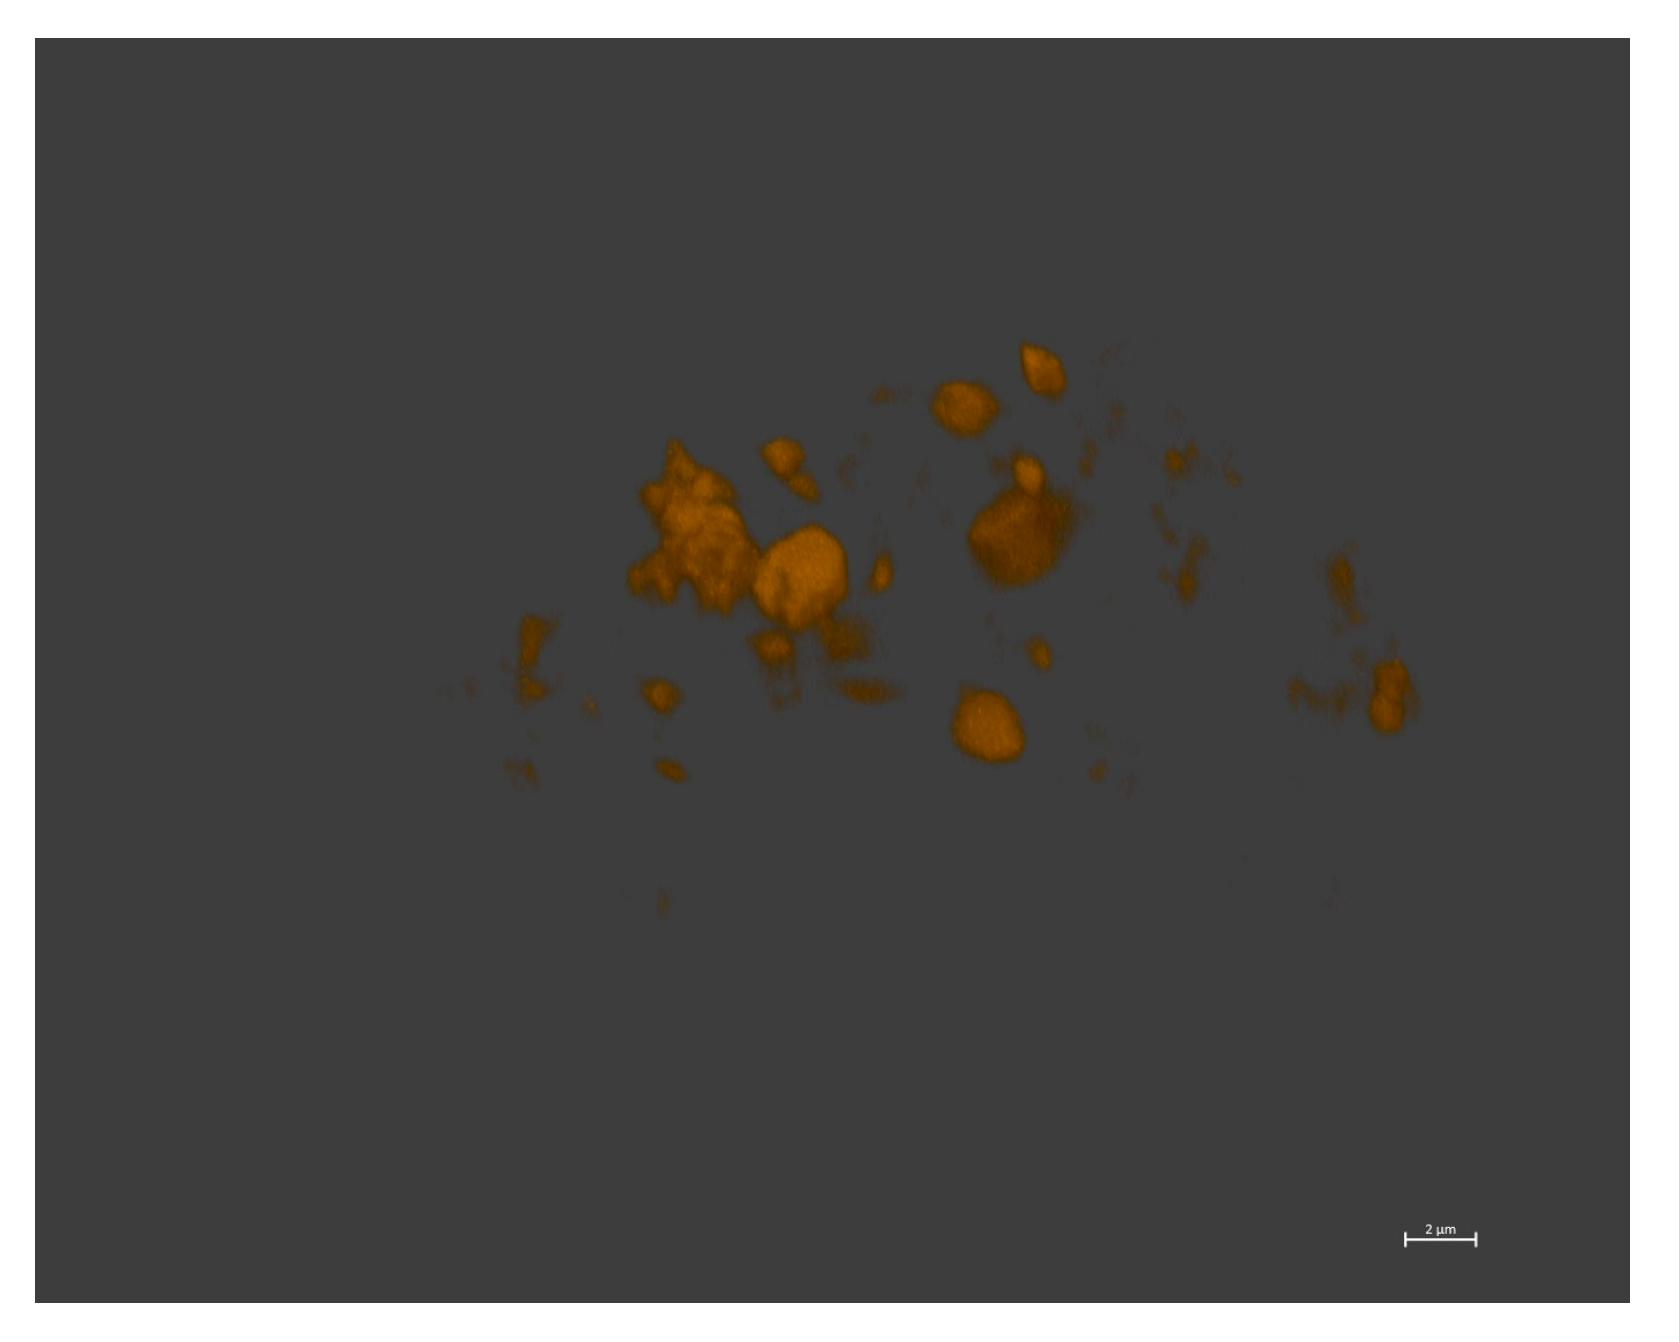

2.2.3. Preparation and Characterization of Drug-Loaded Polymersomes

3.2. Preparation and Characterization of Drug-Loaded Polymersomes